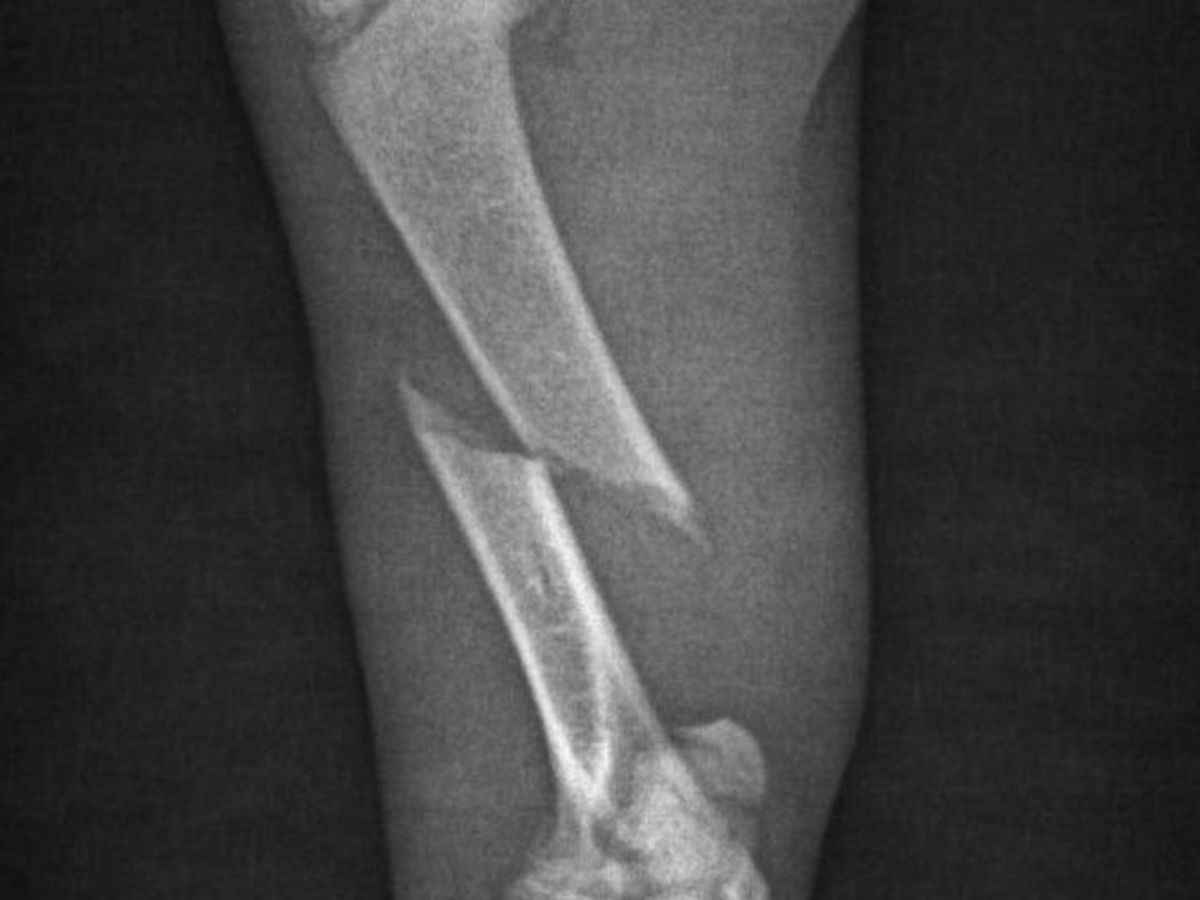

Nach längeren Warten, bekam ich dann die Nachricht mit dem Röntgenbild, wo man deutlich sehen kann das es ein bruch ist und Operiert werden muss.